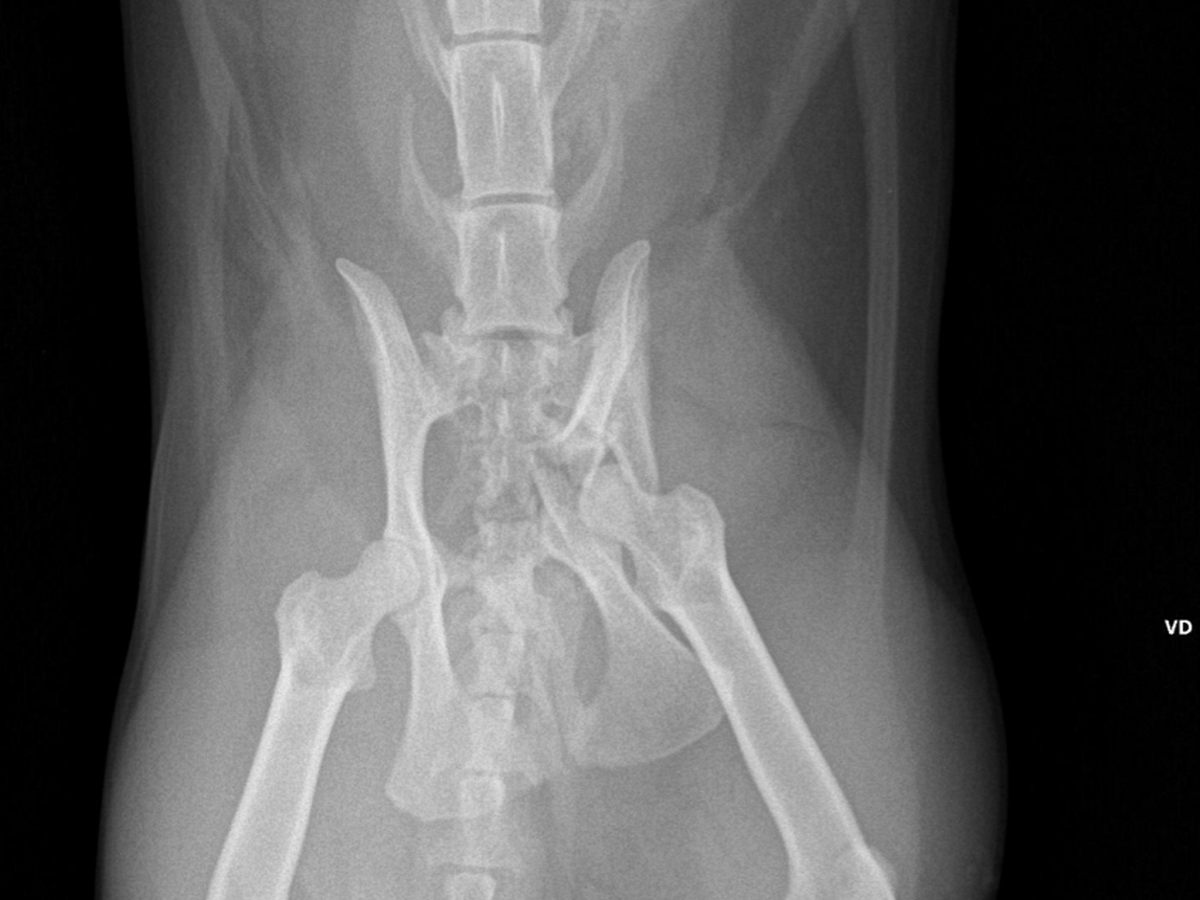

Recently, Kali chewed through the fence of her cat patio and escaped. When I found her, her leg was numb. At the vet, I learned she suffered a severe pelvic fracture—an injury that won’t heal on its own and requires surgery. Without it, she may never be able to move her right leg again.

Kali is having part of her pelvis removed, and it will be replaced with a flexible metal plate. It’s a major surgery — and, unfortunately, it comes with a major price tag.